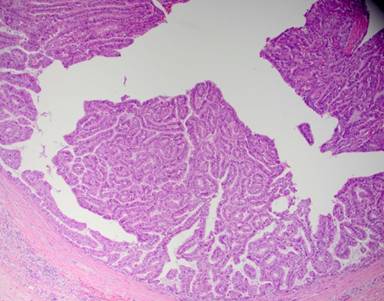

Final pathology showed diffuse PGA, morphologically and immune histochemically identical to the gallbladder primary. The entire length of the pancreatic duct was involved with intraductal exophytic papillary tumor with only a single focus of tumor invasion into the pancreatic parenchyma (Figure 8). All peripancreatic lymph nodes (0 of 10) were negative for malignancy. Gemcitabine and cisplatin were initiated again postoperatively. Patient was noted to have a new liver metastasis six month later. Systemic chemotherapy was switched to FOLFOX, but the disease continued to progress. The patient died of metastatic disease nine months after her total pancreatectomy (three years after her initial diagnosis).

Figure 8. Papillary adenocarcinoma growing along the pancreatic duct with identical histology to original gallbladder primary. |

To our knowledge, this is the first report of resected invasive/metastatic PGA recurring in the entire pancreatic duct and with disease confined only to the pancreas. We hypothesize that papillary tumor cells spread to pancreatic duct via the common bile duct around the time or after initial surgery, but cancer cells remained dormant for nearly two years. This theory is further supported by finding no evidence of peritoneal disease or metastatic lymph nodes during subsequent pancreatectomy. Based on our experience, aggressive surgical approach may prolong survival in well-selected patients with advanced PGA’s.